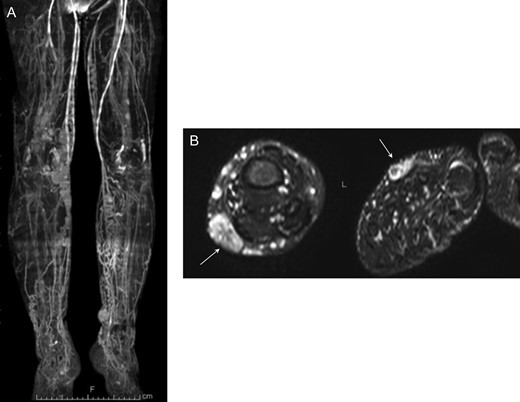

MR venography confirmed dilation of superficial lower limb veins (A). STIR MR imaging detected high signal intensity mass (arrows) indicating multiple lymphovascular malformation in subcutaneous fat layer of bilateral feet (B).